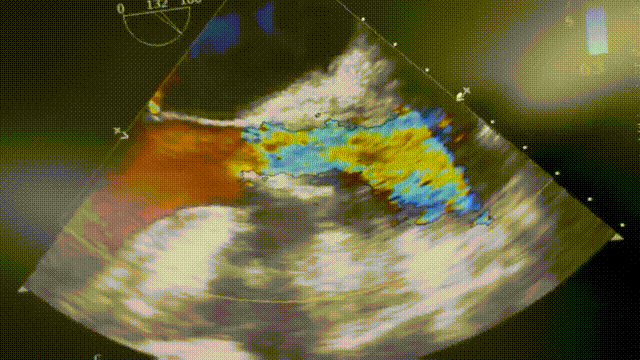

术后即刻评估:

术后超声评估,血流动力学得到显著改善,手术效果理想。

术后评价

患者瓣叶钙化严重,钙化不均匀、瓣口面积严重狭窄是本例手术面临的主要挑战,瓣周漏、瓣环撕裂风险高;不对称性重度钙化,产生移位可能性较大,对瓣膜释放时的定位带来了不确定性。术中初始定位选择0位,瓣膜释放后,瓣膜位置稳定,但存在显著瓣周漏及反流,决定先使用18mm TaurusAtlas球囊后扩,效果欠佳,再使用20mm TaurusAtlas球囊后扩,第二次后扩瓣膜形态完全展开,血流动力学得到显著改善,瓣周漏消失,仅为微量反流,取得了良好的术后结果,使得患者在这次手术中得到了最大获益。